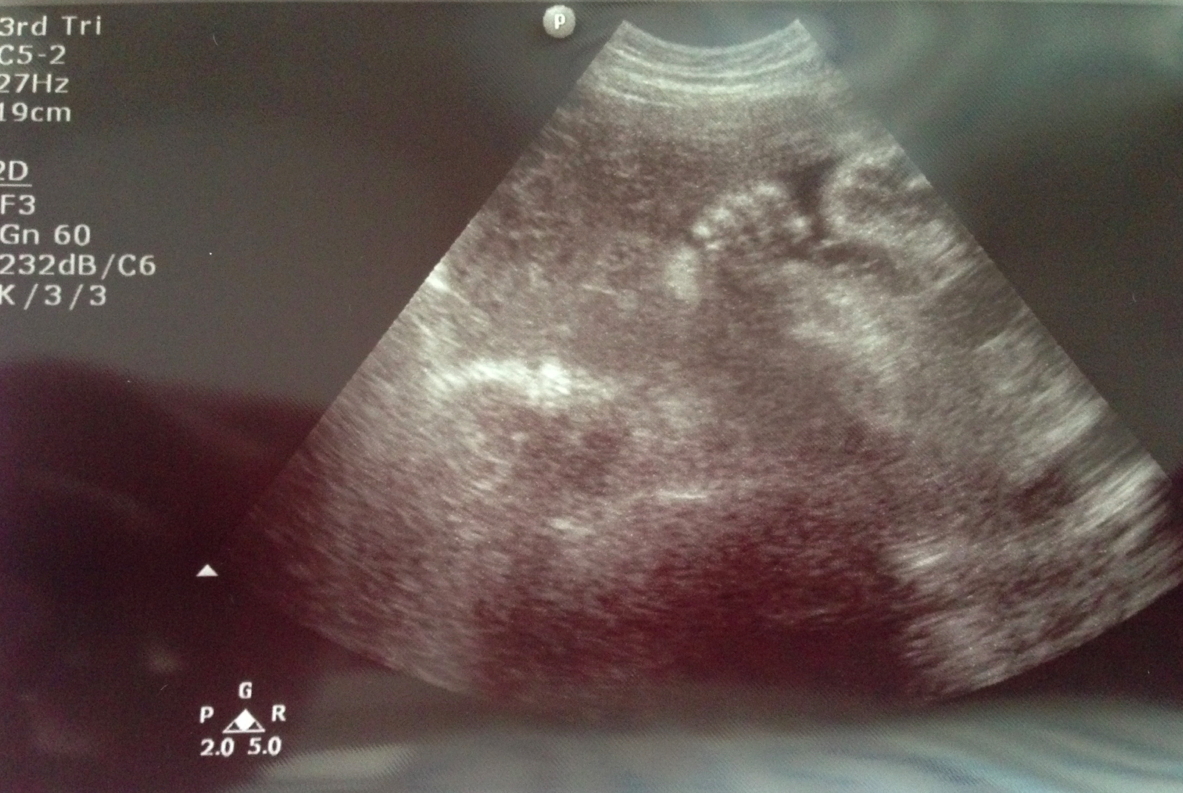

除咗睇到BB呱嘅生長之外,係螢光幕上嘅佢非常活潑呢,有烏蠅手郁郁郁~

仲有郁郁郁嘅腳仔~睇到我哋都笑咪咪呢~